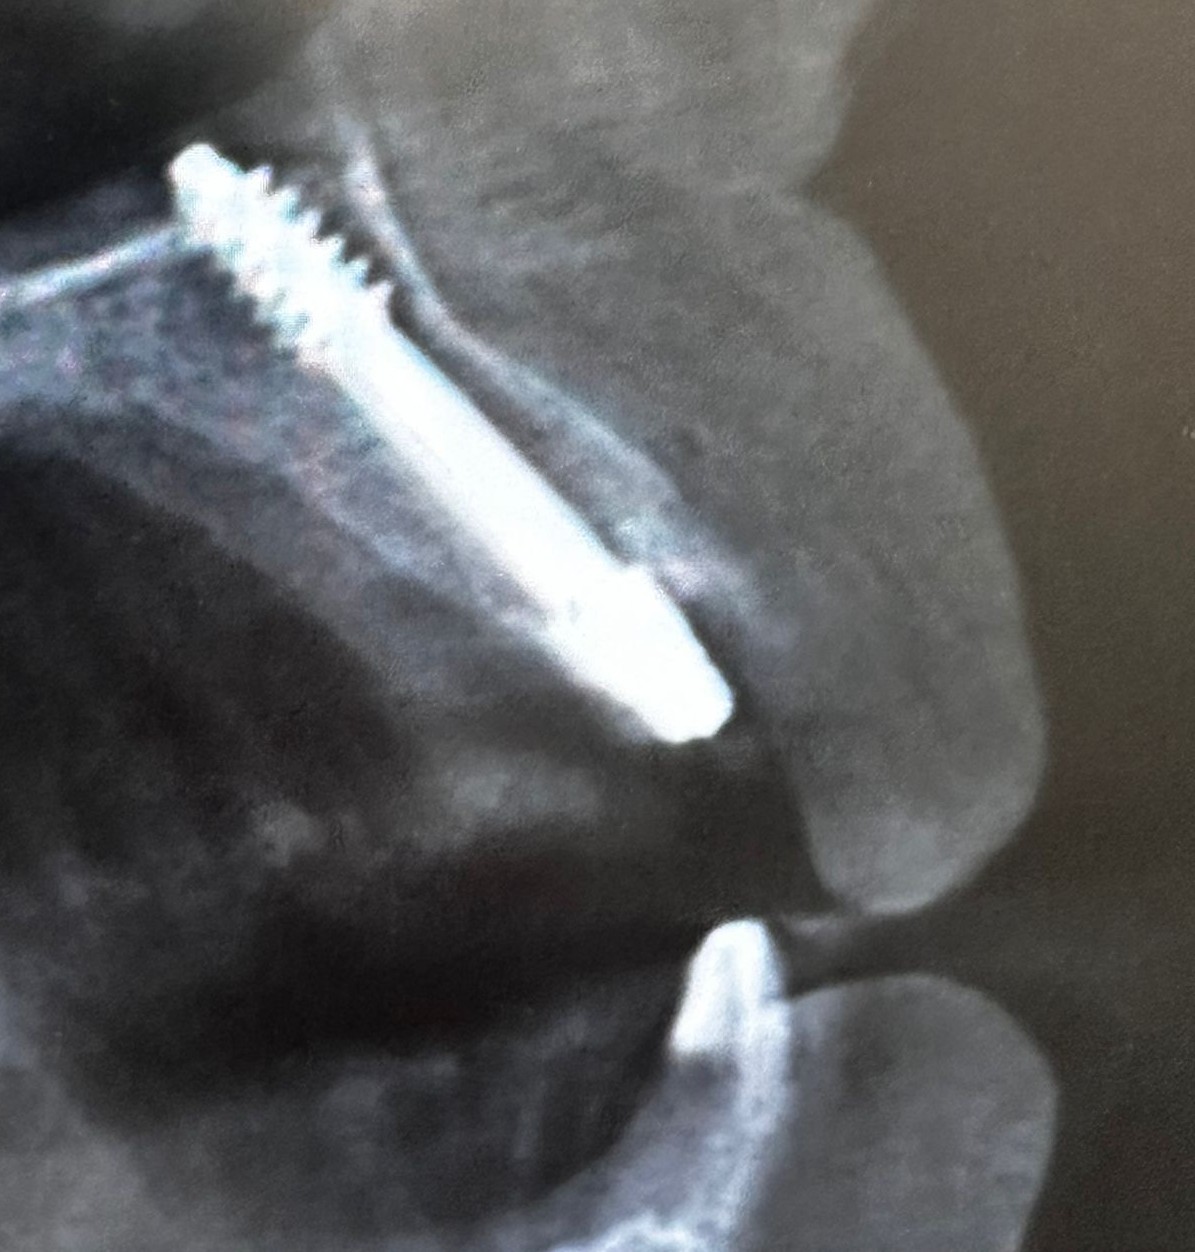

Realizamos la extracción de los cuatro incisivos superiores y, en el mismo acto quirúrgico, colocamos cuatro implantes de anclaje basal de 23 mm, buscando apoyo en el hueso cortical, el hueso más denso y estable. Además, se realizó una soldadura intraoral para rigidizar el conjunto y aportar máxima estabilidad desde el primer momento.